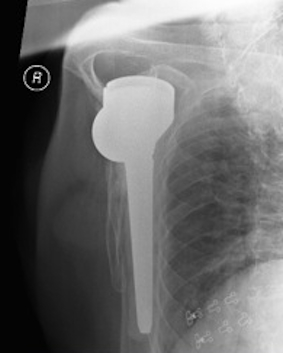

Instability / Dislocation

Dislocated Reverse TSRDislocated Reverse TSR Lateral

disdis

Early dislocation issues

Soft tissue tension  Axillary nerve palsy Component position  Component size

Humeral distalization

- increased liners

- longer humeral body

Inferior base plate  / inferior impingement

Increased glenosphere size increases jump distance

Glenoid lateralization

- lateralized glenosphere

Subscapularis

Late dislocation

Liner wear

Heterotopic ossification

Revision